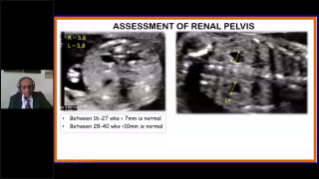

AlimentÊe par la plateforme avancÊe ZST+, la gamme complète de solutions intelligentes Nuewa est con?ue spÊcialement pour amÊliorer la santÊ des femmes avant, pendant et après la grossesse, de manière à poser des diagnostics complets et efficaces pour rÊpondre à des dÊfis cliniques de plus en plus exigeants.